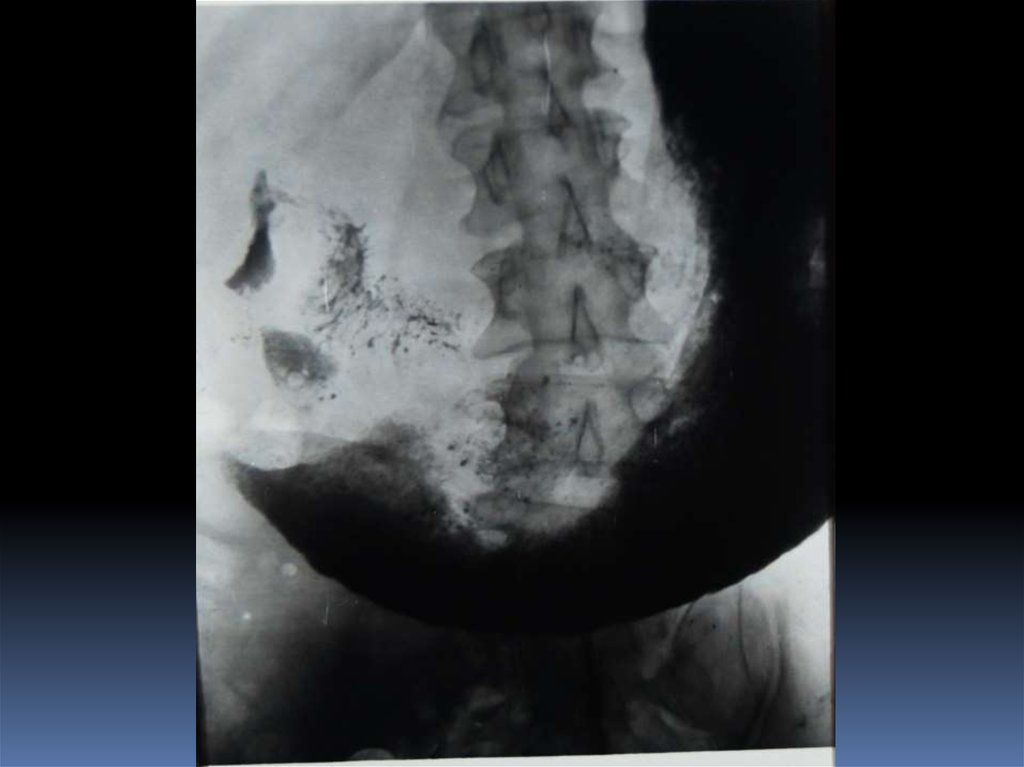

54. Редкие случаи из практики

55.

56.